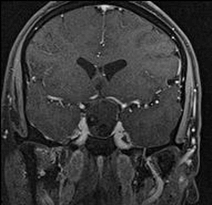

65 year old male with Pituitary Macroadenoma with cavernous sinus extension. Endoscopic Transsphenoidal Surgery done with Intraoperative MRI showing residual tumor in the cavernous sinus region under the left carotid artery. Post op MRI showing on the right no residual tumor in the sinus. (T1 contrast above and T2 coronal sections below).

Excision of pituitary tumors is achieved well in most cases. But in Macroadneomas with lateral and superior antreo- posterior extensions it is difficult to achieve total excision. This would usually necessiate Radiotherapy at later date. Radiotherapy has higher chance of Hypopituitarism too. If intra-operatively the residual tumor is seen with MRI, then total excision can be possible in almost all the cases. This would avoid unncessary radiation in these patients with benign tumors. This also increases preservation of normal functioning pituitary gland. It is invaluable in functioning adenomas where surgery has the highest chance of cure.